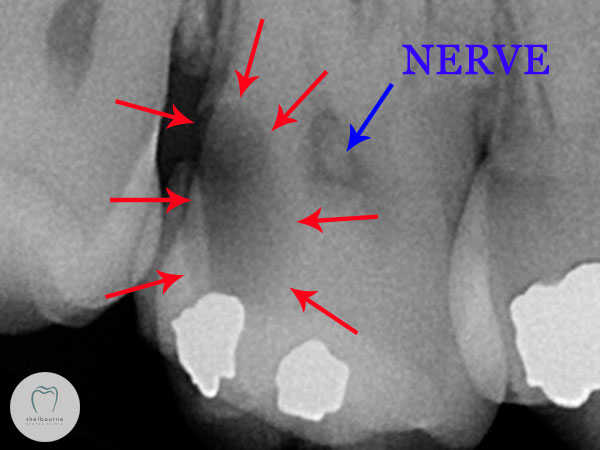

So having run out of other ideas and still unsure which tooth is the suspect, I took a digital x-ray. This lets me see what’s going on between teeth in particular, and under old fillings to some extent. And there we have it, a big dark decayed area on the back of the second molar.

I’ve highlighted the area on the image below as not everyone is used to reading x-rays! The red arrows show the decayed area. The blue arrow points to a separate dark area; that’s the nerve. This decay is way too close for comfort.